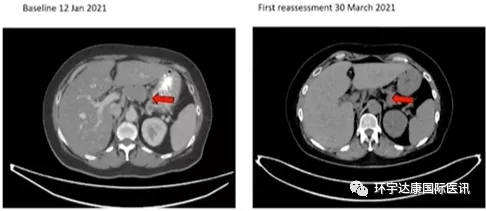

CART-RGFR细胞治疗之前和1、3、10和15个月患者1的CT扫描图像。

红色箭头表示原发肿瘤和腹膜后淋巴结转移。